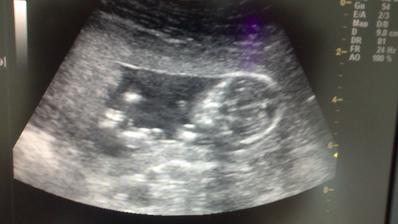

* 29.4.2014 objednané vyšetření v Centru lékařské genetiky - UZ na vývojové vady, tak snad to dopadne dobře - Tak dnešní screening dopadl na 1*... Všechno naprosto dokonalé, miminko zdravé, testy i UZ v pořádku. Mimčo měří 6 cm. Bylo krásně natočené a mávalo nám ručičkama. Paní doktorka nám vše krásně vysvětlila a ukázala... Manžel byl nadšený a je pyšný, protože budeme mít na 80% holčičku 🙂 Jsme nesmírně šťastní 🙂